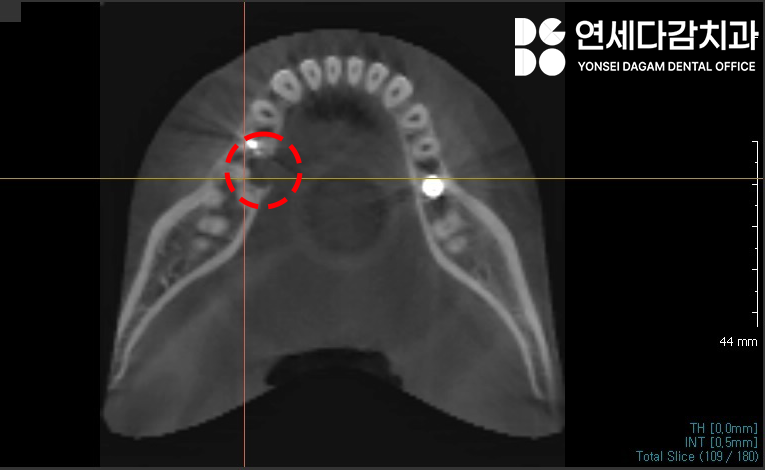

2023.12.18

연세다감치과 에서 수술 전

촬영한 CT사진입니다.

2차원 파노라마 뿐만 아니라

3차원 CT를 통해

매복된 정도와 위치를 정확하게 파악한 뒤,

주변 구조물이 손상되지 않도록

조심스럽게 뽑는 것이 중요합니다.

과잉치의 정확한 위치를 찾아낸 뒤

설측으로 잇몸을 절개하여 당일 발치를 마쳤습니다.

이 케이스의 경우 다행히

설신경과 어느정도 거리가 있었습니다만,

통상적으로 설측 매복 과잉치 를 뽑아낼 땐

설신경을 신경쓰며

점막 거상 (retraction) 및

발치를 진행해야됩니다.